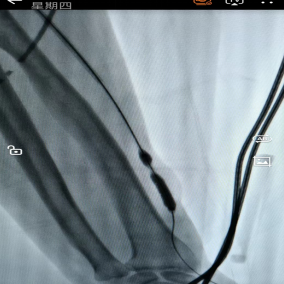

多年来,贵州航天医院各科室紧跟医学前沿,不断强技术、补短板,大力开展新技术、新项目,完成了许多高精尖、高难度、本地区“首例”的技术,填补了医院医疗技术空白,满足了群众日益增长的医疗需求。 本期,我们将为大家带来肾脏风湿科特色技术——动脉瘤、囊样扩张等切除+原位内瘘重建术。 案例分享 患者在6年前确诊尿毒症并开始进行血液透析,在入院前2天,发现右前臂出现包块,故前来我院肾内科就诊。在为患者完善了彩超等检查后,诊断为:慢性肾脏病5期,右前臂内瘘处动脉瘤形成,内瘘功能丧失。 考虑到患者曾行“冠心病+PCI术”,长期口服华法林治疗,监测凝血功能INR升高,手术中出血风险较大,在征得患者及其家属同意后,待其凝血功能INR正常后,为其实施动脉瘤切除+原位内瘘重建术。 因患者手术切口长、难度大,科室团队通过充气压脉带充气加压阻断血运,在右前臂距腕关节上约10cm处,沿动脉瘤皮肤表面纵行呈弧形切开2条长约9cm切口,内瘘吻合口静脉端见一30×20mm包块及多处小包块,经过认真,仔细的操作,最终成功为患者分离动脉瘤、脓性分泌物及坏死组织,并完成原位内瘘重建。术后,患者定期换药消毒,恢复良好。 开展动脉瘤、囊样扩张等切除+原位内瘘重建术,手术医生需经过相关专业培训,手术难度大,操作要求高。目前,贵州航天医院肾脏风湿科完全具备手术资质,已为遵义地区许多患者提供该项医疗服务,极大帮助患者节约了血管资源,减轻了因临时透析导管带来的痛苦及相关导管风险。 什么是动脉瘤、囊样扩张等 切除+原位内瘘重建术 自体动静脉内瘘是维持血液透析患者血管通路的首选方法,如果因为内瘘吻合口临近或穿刺部位形成血管瘤、囊样扩张,经过保守治疗效果不佳者,可采取动脉瘤、囊样扩张等切除,并重建动静脉内瘘。 动脉瘤、囊样扩张等切除+ 原位内瘘重建术原理 尿毒症患者动静脉内瘘术后,血液动力学的改变,经反复穿刺,导致内瘘吻合口临近或穿刺部位形成血管瘤或囊性扩张,严重时可出现动脉瘤破溃、感染等严重并发症,内瘘失功,对保守治疗效果不佳者,采取动脉瘤、囊样扩张等切除,并在原位重建动静脉内瘘。 动脉瘤、囊样扩张等切除+ 原位内瘘重建术优势 动脉瘤、囊样扩张等切除+原位内瘘重建,新内瘘成熟时间短,在短期内即可使用(约术后1周),大大提高了治疗成功率,并为患者节约血管资源。 血管通路是尿毒症维持性血液透析患者的生命线,而动脉内瘘是最重要也是最经济有效的血管通路。随着透析时间延长,部分患者内瘘血管出现动脉瘤,随时可能破裂大出血危及生命,内瘘也因此失去功能。此技术能解决内瘘动脉瘤所带来的危险,同时重建内瘘功能,对延长透析患者的生存时间,提高透析患者的生活质量具有重大意义。 贵州航天医院肾脏风湿科 专家团队 冯远军 肾脏风湿科主任 主任医师 临床擅长:对慢性肾脏病、急性肾损伤、急慢性肾小球肾炎、肾病综合症、风湿性疾病、间质性肾炎、肾小管损伤等疾病的诊治及血液透析技术、动静脉内瘘成形术及疑难病例的诊治具有丰富的临床经验。 曾在上海市第一人民医院及贵阳市第一人民医院进修学习,贵州省医学会肾脏病学分会第五届委员会委员,遵义市医学会肾脏病学分会第一届委员会副主任委员,遵义市医学会风湿病学分会第一届委员会副主任委员,荣获“贵州航天劳动模范、遵义市汇川区先进工作者”,遵义市医疗事故鉴定专家库成员,主持省市级科研项目4项,完成4项,近5年发表论文10余篇,北大核心期刊1篇。 王卫华 肾脏风湿科 主任医师 临床擅长:从事临床工作28年,擅长尿毒症患者血管通路的建设及维护(如标准和高位动静脉内瘘术、取栓+内瘘重建术、内瘘狭窄球囊扩张术、长期中心静脉置管术及肾穿刺活检术)等手术,对原发性和继发性肾病综合征、急、慢性肾小球肾炎、慢性肾脏病、泌尿系感染、结缔组织病、急性中毒、痛风、贫血、血小板减少症等疾病诊治及血液透析技术应用等具有丰富的临床经验。 1995年毕业于遵义医学院临床医学系,曾前往重庆医科大学进修学习肾脏疾病及血液净化;遵义市医学会肾脏病学分会常务委员,遵义市血液净化质量控制中心委员;先后发表肾病专业省部级医学刊物医学论文8篇,主持市级科研项目2项。 李丽华 肾脏风湿科 副主任医师 临床擅长:从事临床工作17年,对慢性肾脏病、急性肾损伤、急慢性肾小球肾炎、肾病综合征、风湿性疾病、间质性肾炎、肾小管损伤、急慢性肾衰竭的血液透析、CRRT治疗以及血管通路的建设维护等具有丰富的临床诊疗经验。 2006年毕业于遵义医学院临床专业,曾在遵义医学院附属医院完成住院医生规范化培养,并前往第三军医大学新桥医院、珠海市人民医院进修学习;中华医学会遵义市肾脏病学分会委员,遵义中医药学会肾病专业委员会委员,遵义市血液净化质量控制中心委员,遵义市医学会血液学分会委员会委员;发表省部级医学刊物医学论文4篇,主持参与省级科研课题1项,主持参与市级科研课题1项,院级新技术6项,获得本专业授权实用新型专利3项。 李 玫 肾脏风湿科 副主任医师 临床擅长:从事临床工作15年,对慢性肾脏病、急性肾损伤、急慢性肾小球肾炎、肾病综合征、风湿性疾病、间质性肾炎、肾小管损伤等疾病的诊治具有丰富的临床经验,擅长血液透析技术、动静脉内瘘成形术等。 2008年毕业于遵义医学院临床医学系,曾前往遵义医学院附属医院进修学习肾脏病与血液净化相关技术;遵义市医学会肾脏病学分会委员,发表肾病专业省部级医学刊物医学论文4篇。 贵州航天医院肾脏风湿科简介 贵州航天医院肾脏风湿科2017年建立,住院患者承载能力达到50人左右,透析治疗服务惠及250余人的患者群体,在学科建设、高端医疗设备引进及专业技术队伍已达到区域内领先水平。科室共有医护人员46名,副高级以上专家7名,亚专业设置齐全,涵盖肾脏疾病、风湿免疫疾病药物治疗、透析治疗及透析通路维护等多个专业领域,为患者提供全面、精准、高效的诊疗服务。配备了尖端的医疗设备与智能化的辅助系统,包括透析机、CRRT机等设备。 • ✦ 专科特色 ✦ • (一)肾脏病治疗领域:专精于血液透析、血液透析滤过、血液灌流、血浆置换、CRRT等尖端技术,致力于为患者量身打造个性化的肾脏替代治疗方案。 (二)在风湿病治疗方面:凭借生物制剂、免疫抑制剂等前沿药物,结合患者的具体情况,精心策划个体化的治疗策略,有效减轻患者症状,显著提升生活质量。 超声引导下球囊扩张术:内瘘狭窄是内瘘最常见的并发症之一,我们采用先进的超声引导下球囊扩张术,通过微创方式恢复内瘘通畅,有效避免了传统手术带来的创伤和痛苦。 内瘘血栓溶栓治疗、取栓术:血栓形成是内瘘功能丧失的主要原因之一,根据患者具体情况,采用溶栓治疗、取栓术等多种手段,确保患者及时恢复透析治疗。 内瘘动脉瘤形成治疗:动脉瘤是由于内瘘局部血流动力学改变引起的血管扩张性疾病,采取佩戴弹力绷带、手术修复等措施,防止动脉瘤进一步发展和破裂。 内瘘感染治疗:内瘘感染是内瘘并发症中最为严重的类型之一,一般采用敏感抗生素进行抗感染治疗,严重者采取手术清创等措施。 内瘘窃血综合征治疗:是由于内瘘建立后,远端肢体血流减少引起的一系列症状,通过调整透析方案、改善内瘘血流分布及必要时重建内瘘等措施,有效缓解患者的症状并提高其生活质量。 • ✦ 诊疗范围 ✦ • 擅长治疗急慢性肾炎、肾病综合征、肾衰竭等肾脏疾病;擅长治疗类风湿关节炎、系统性红斑狼疮、干燥综合征等风湿免疫性疾病,并为患者提供健康教育与康复指导,帮助患者更好地管理疾病,提高生活质量。